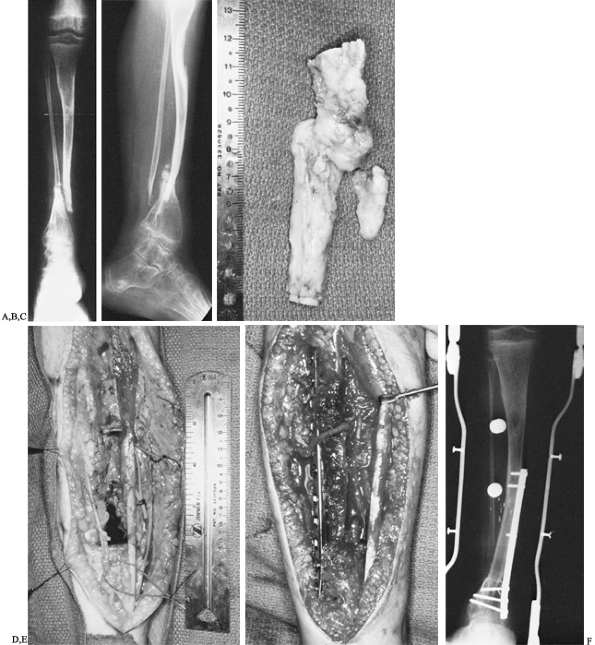

presented with a congenital pseudarthrosis of the right tibia and

fibula that had defied several previous attempts at bone grafting and

immobilization (Fig. 36.4). An extraperiosteal

dissection and excision of the pseudarthrosis of the tibia and fibula

were performed, resulting in an 8-cm tibial defect. A buttress plate

was used to secure the graft to the tibia proximally and distally. Six

months postoperatively there was good incorporation of the fibula graft

proximally as well as distally. The patient subsequently required a

contralateral epiphysiodesis to equalize a leg length discrepancy and

an osteotomy of the tibia to correct valgus bowing.

Figure 36.4. A: Anteroposterior radiograph of an 11-year-old boy with von Recklinghausen’s disease and congenital pseudarthrosis of the tibia. B:

Lateral radiograph demonstrating a proximally as well as distally bowed tibia along with marked osteoporosis of the distal tibia and foot. C: Intraoperative photograph of resected specimen, including tibial and fibular pseudarthrosis. D: Intraoperative photograph demonstrating bony defect. Vessel loops are noted around the anterior neurovascular bundle as well as the saphenous vein. E: Intraoperative photograph demonstrating buttress plate. The vascular pedicle can be seen transversing the proximal portion of the plate into the graft. F: Radiograph of leg 6 months postoperatively, demonstrating sound union of the vascularized graft. However, tibial bowing was noted.  |